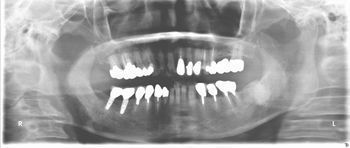

下顎のフルインプラントです。6本のインプラント(4本では不安です)を埋入して上部構造はスクリュウで固定してます。下の総義歯はみなさんどうしても浮き上がってきて食べにくいです。インプラントを埋入して即時負荷をかけるのはどうかと思いますが、骨と結合した後ならかなり頑丈な上部構造ができて、硬いものでも噛みやすくなります。

●● 様 男性 70代

治療の期間・回数:6か月、10回

治療の価格:150万円/下顎

治療のリスクや副作用:手術後に、痛みや腫れ、出血、合併症などを引き起こす可能性があります。噛む感覚がご自身の歯と異なる場合があります見た目がご自身の歯と異なる場合があります。手術後にメインテナンスを継続しないと抜け落ちる可能性があります。